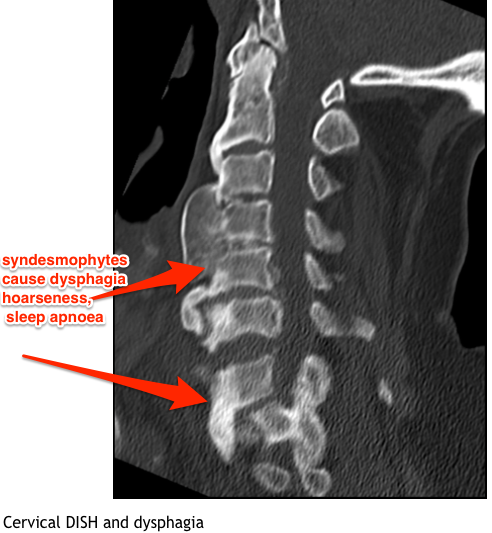

What are syndesmophytes?

Where do syndesmophytes occur?

What are the symptoms and signs of diffuse idopathix skeletal hyperextosis?

Symptoms

What are the complications of DISH?